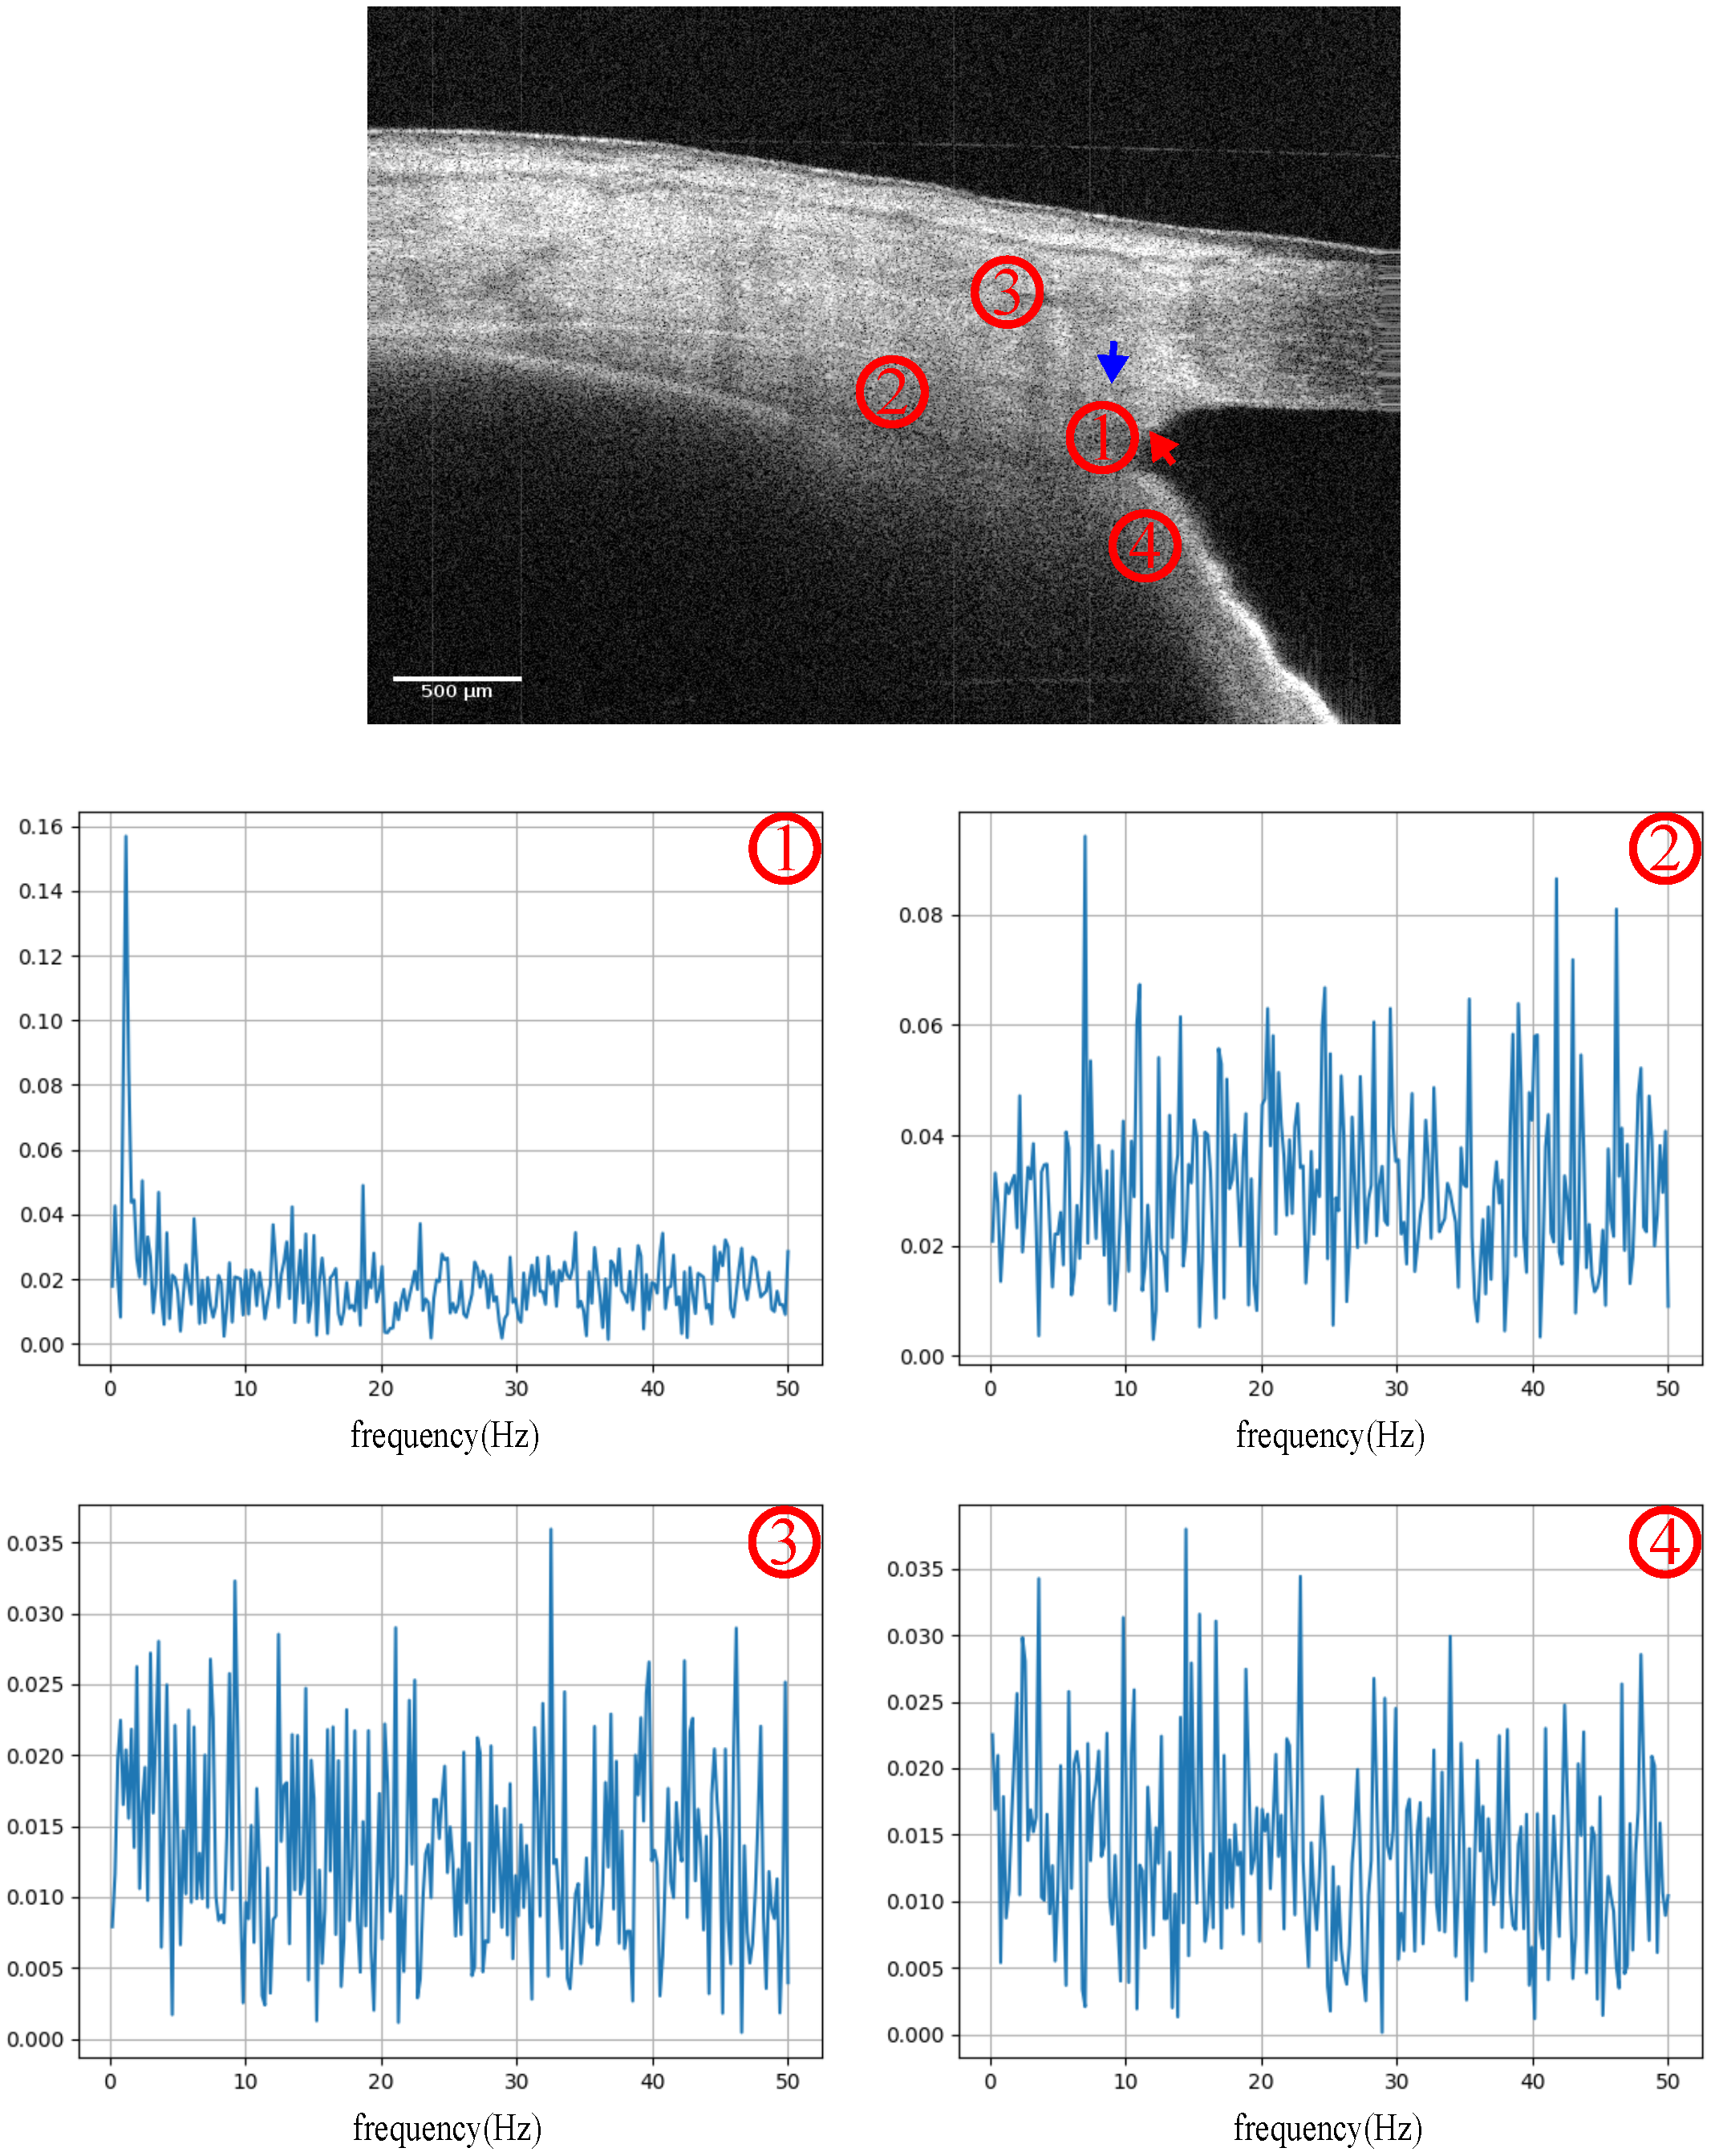

The OCT scanning position was located at the iridocorneal angle, both nasal and temporal. According to the real-time intensity images, the light incident direction was adjusted to the maximum iridocorneal angle degree. A series of cross-section images were recorded in 5 s. Furthermore, the phase signal was decomposed from the fast Fourier transform (FFT) of the OCT. The PhDiff was obtained simply by temporal subtraction of the contentious frames (pair of B scans). To remove the bulk motion, image registration based on the corresponding intensity image and phase compensation were implemented in advance. Figure 3 shows the frequency spectrum of signals sampled in specific regions of the iridocorneal angle, which included the TM-SC region, ciliary body, cornea and iris. Significantly, the fundamental frequency of the PhDiff signal in the TM-SC region was in the range of 1–2 Hz, the same as that of the heartbeat rate.

Figure 3. Frequency spectrum of the PhDiff signal sampled on the iridocorneal angle, including ➀: the trabecular meshwork and Schlemm’s canal adjacent region; ➁: the ciliary body region; ➂: the corneal region; and ➃: the iris region. The red arrow points to the trabecular meshwork, and the blue arrow points to the SC. The unit of the horizontal axis of the frequency spectrum graphic is Hertz.